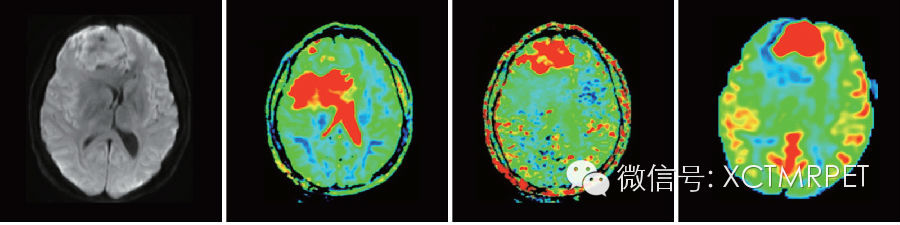

上图从左至右分别是DWI原始图像、Slow ADC后处理图像、Fast ADC后处理图像、3D ASL灌注图像。Slow ADC 反映的是组织的水分子扩散特性,而Fast ADC反映的是灌注特性,提示该肿瘤为高灌注的,与3D ASL 结果吻合。

GE 独有的eDWI 后处理分析可以提供不同的参数信息,这些信息提供了病变的不同特性,因而在临床上具有不同的临床意义。